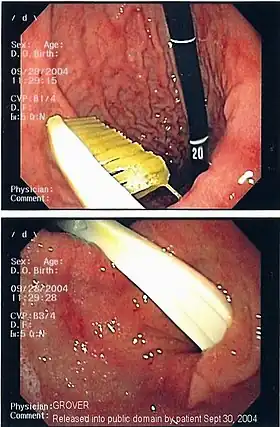

An endoscopy image of the stomach, showing a foreign body in the form of a toothbrush.

One of the most common locations for a foreign body is the alimentary tract.

It is possible for foreign bodies to enter the tract from the mouth or rectum.